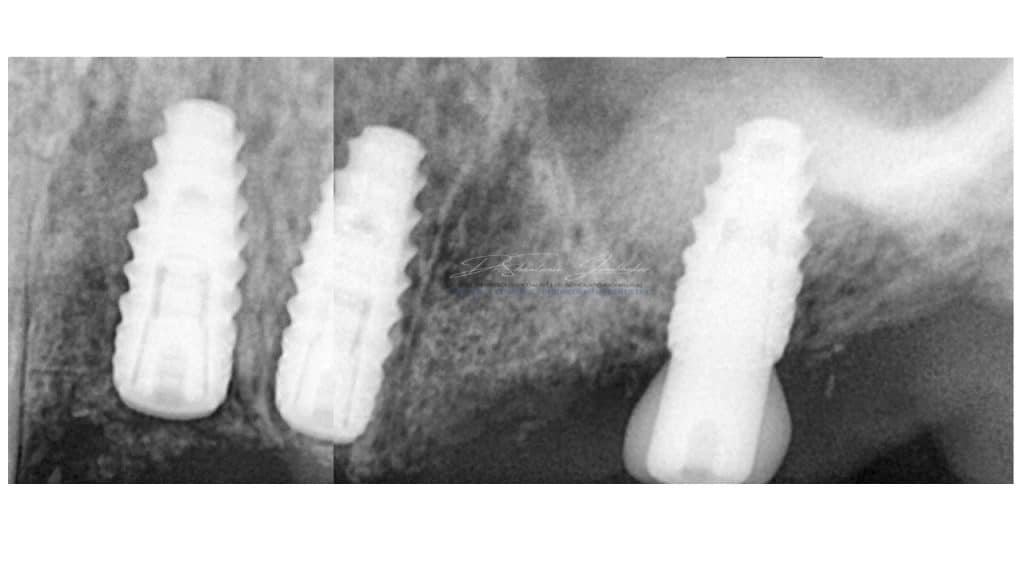

Radiographic examination revealed radiolucent lesion with 23,25 and reduced residual ridge dimensions with sites 26 & 27. Cone beam CT (CBCT) evaluation was performed for available quantity & quality of bone at the proposed implant sites using CS 3D Software.

IOPA at 22 month Follow up